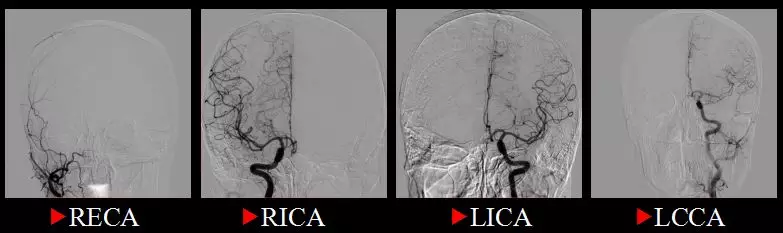

2017-7-26:患者平卧于DSA复合手术床上,全麻成功后,双侧腹股沟常规消毒铺巾,以Seldinger技术穿刺右股动脉,置入5F导管鞘,导丝支撑下,将5F导引导管超选入右侧椎动脉内,复查造影证实颅颈交界处肿瘤明显异常染色,主要由右侧椎动脉肌支和脑膜后动脉供血,旋转后选择工作角度,在Traxcess 0.014微导丝支撑下将Echelon-10微导管超选入右侧椎动脉肌支,手推造影证实远端无正常血管后以5%葡萄糖溶液冲洗管腔,然后路径图下用15%Glubran胶缓慢栓塞此处血供,注入约0.4ml栓塞剂后出现返流,停止注射,撤出微导管。

然后用同样方法将另一根Echelon-10微导管超选入脑膜后动脉,同法注射Glubran栓塞剂约1ml,见栓塞剂在肿瘤内部弥散理想,复查造影见左侧椎动脉肿瘤血供完全栓塞,撤出微导管,再将导引导管超选入左侧椎动脉,复查造影发现肿瘤尚有少量来自左椎动脉的血供,但无合适栓塞动脉,肿瘤血供总体栓塞约80%,留鞘行开颅肿瘤切除术。